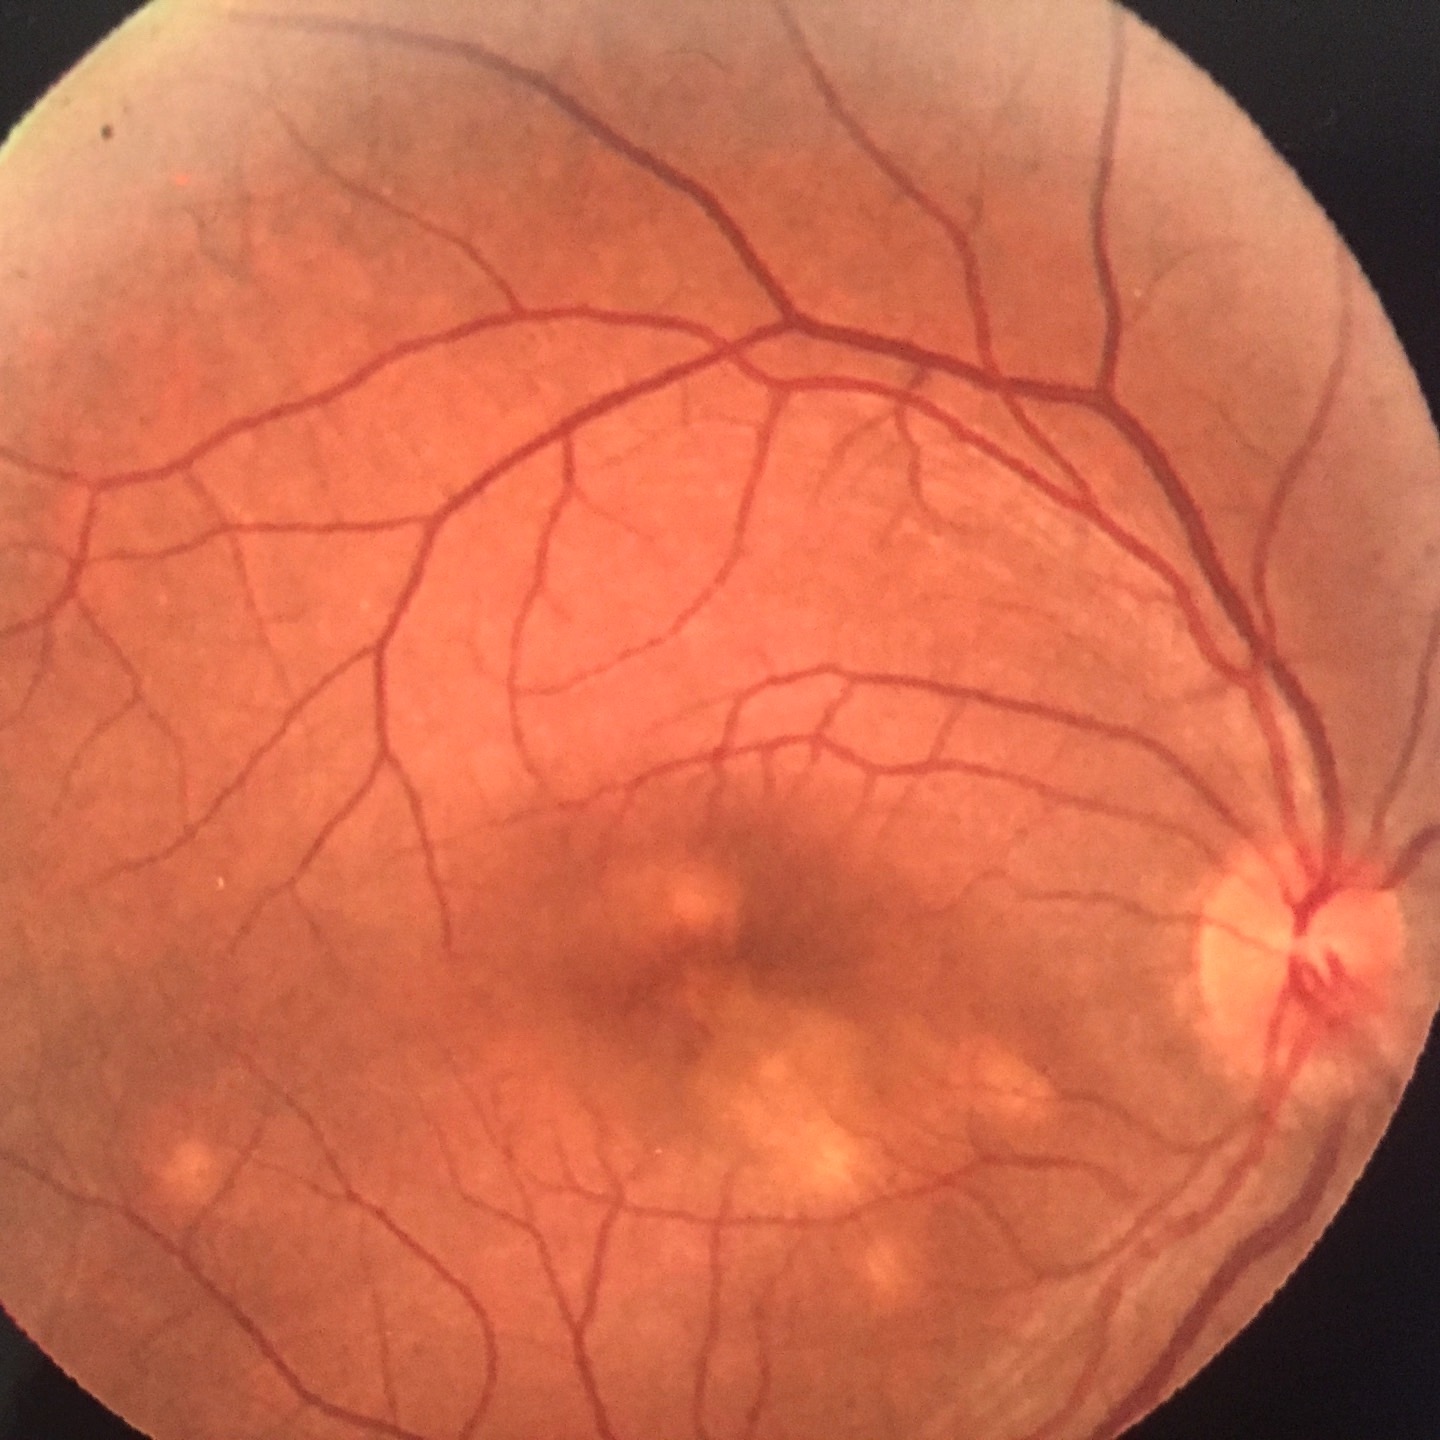

- pathologies rétiniennes (DMLA, diabète, myopie forte...)

Fond d'oeil : corps flottants, myopie forte, trou/déchirure de rétine, myodesopsie

Pathologies rétiniennes : DMLA - dégénérescence maculaire liée à l'âge, diabète, myopie forte, occlusion veineuse...